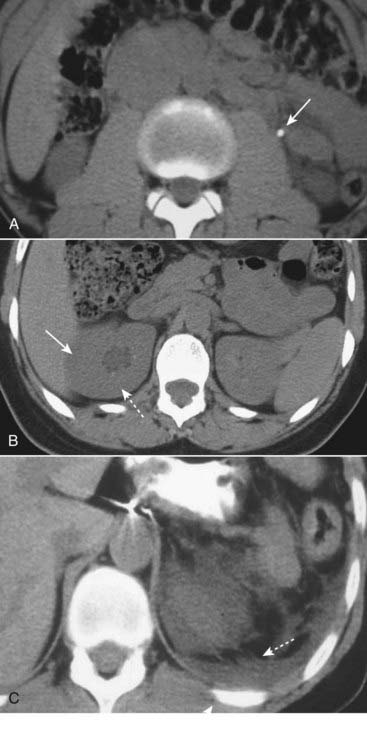

Figure 16-8 Imaging findings of ureteral calculi, three different patients.

A, A calcified stone is seen in the left ureter (solid white arrow). B, Hydronephrosis is present on the right (dotted white arrow) with overall enlargement of the right kidney (solid white arrow). C, There is considerable perinephric stranding (dotted white arrows) and fluid that has leaked from the kidney (solid white arrow), most likely from a rupture of one of the renal fornices.